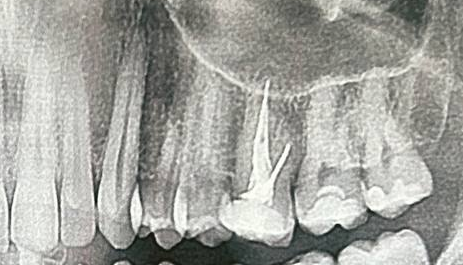

Тебе снимок КТ делали или обычный черно-белый? На КТ и кариес виден (но могут быть погрешности) и киста

Аноним 20/08/25 Срд 15:35:12 1636988 68

>>1636840

Нет кариеса. Я делал снимок. У меня под кожей только 1 восьмерка. Я вычищаю над ней пространство. Там налет постоянно накапливается. Ночью раз в сутки чищу ерщиком

Болит уже года 2-3 (ну и чистить начал только года 2-3 назад.

Т.е. если бы кариес был он бы за эти годы развился очень сильно

Аноним 20/08/25 Срд 15:36:41 1636990 69

>>1636970

Обычный рентген.

Но у меня не как пикрил.

У меня восьмерка. Последний зуб. Соседняя семерка в норме. Т.к. чищу под кожей над восьмым зубом сверху

Аноним 20/08/25 Срд 15:40:20 1636993 70